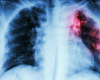

Bu gün həyati təhlükəsi olan 20-dən çox xəstəliyin qarşısını almaq üçün peyvəndlər mövcuddur. Onların sayəsində istənilən yaşda insanlar daha uzun və sağlam ömür sürə bilirlər.

Peyvəndin qarşısının alınması bəşəriyyətin ən böyük nailiyyətlərindən biridir. Bu, bir çox yoluxucu xəstəliklərin yayılmasının qarşısını almağa və əhali arasında ölüm nisbətini azaltmağa kömək edir. Bundan əlavə, peyvənd həm də xəstəliklərin və əlilliyin müalicəsi xərclərini azaldaraq əhəmiyyətli iqtisadi təsir göstərir.

Hər il peyvənd difteriya, tetanus, göy öskürək, qrip və qızılca kimi xəstəliklərdən 3,5-5 milyon ölümün qarşısını alır. Peyvənd ilkin səhiyyə xidmətinin əsas komponentlərindən biridir və immunizasiya hüququ hər bir insanın ayrılmaz hüququdur.